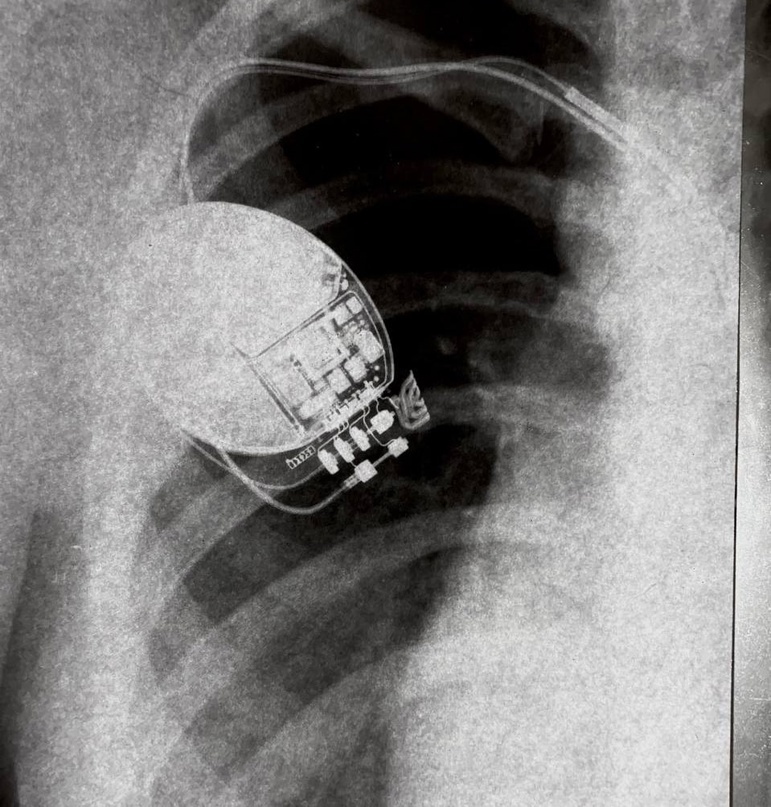

Моя мама ехала в поезде с Москвы домой, знакомиться с женщиной именующей себя “Ведьма”. Целью визита в Москву - был поход к врачу кардиологу и сдача генетического теста, для того чтобы понять откуда у меня, генетическая болезнь сердца.

«Фото моего прибора»

“В 15 лет на фоне полного здоровья у меня случается несколько остановок сердца, после чего мне имплантируют прибор Кардиовертер-дефибриллятор”